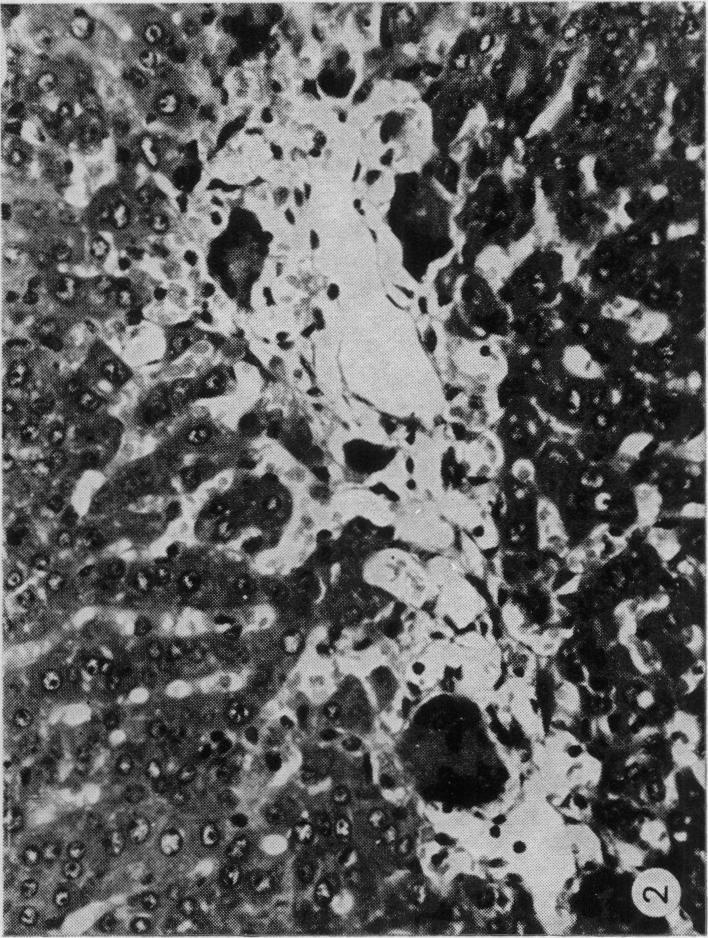

Male Syrian hamsters, 8-10 weeks of age, were treated with a single intraperitoneal injection of crystalline aflatoxin B1 in solution of N -N -Dimethylformamide (DMF). The concentrations of aflatoxin were adjusted to the smallest controllable amount of solvent in relation to the size of the animal (0-5 or 1-0 ml/kg). Treatment with, respectively, 5-0 or 2-5 mg/kg aflatoxin in 1-0 ml/kg DMF was lethal to most animals within one week. However, reduction of the solvent to 0-5 ml/kg, while not eliminating the mortality entirely during the first week, made possible observation of the survivors up to 28 days. Hamsters appear to be more susceptible to DMF poisoning than other species, like rat, guinea-pig and rabbit in which this solvent was used by investigators on the biological effects of aflatoxin. Either dose given of DMF alone was lethal for several animals during the first week of observation and sufficient to produce histological lesions in the liver which were characteristic and clearly different from those induced by aflatoxin during the same period. DMF alone caused centrilobular necrosis which was accompanied by haemosiderosis of liver structures. With a aflatoxin, in addition, periportal and midzonal necrosis of the liver was present. Aflatoxin B1 and B1 and DMF both induce haemorrhagic tendency probably involvement in the coagulation process of the blood. It cannot be decided, however, at present whether this is the result of an indentical mechanism.

8至10周龄的雄性叙利亚仓鼠经腹腔注射一次溶解于N -N -二甲基甲酰胺(DMF)中的结晶黄曲霉毒素B1进行处理。根据动物体型将黄曲霉毒素的浓度调整至溶剂的最小可控量(0 - 5或1 - 0毫升/千克)。分别用1 - 0毫升/千克DMF中5 - 0或2 - 5毫克/千克的黄曲霉毒素处理,在一周内对大多数动物是致命的。然而,将溶剂减少至0 - 5毫升/千克,虽然不能完全消除第一周的死亡率,但使得观察存活者长达28天成为可能。仓鼠似乎比其他物种,如大鼠、豚鼠和兔子,对DMF中毒更敏感,研究人员曾用这种溶剂研究黄曲霉毒素的生物学效应。单独给予任何一种剂量的DMF在观察的第一周内对几只动物都是致命的,并且足以在肝脏中产生组织学病变,这些病变具有特征性且与同期黄曲霉毒素诱导的病变明显不同。单独的DMF导致小叶中心坏死,并伴有肝脏结构的含铁血黄素沉着。此外,黄曲霉毒素还会导致肝脏的门周和中区坏死。黄曲霉毒素B1以及黄曲霉毒素B1和DMF都可能导致出血倾向,这可能涉及血液凝固过程。然而,目前尚无法确定这是否是相同机制的结果。